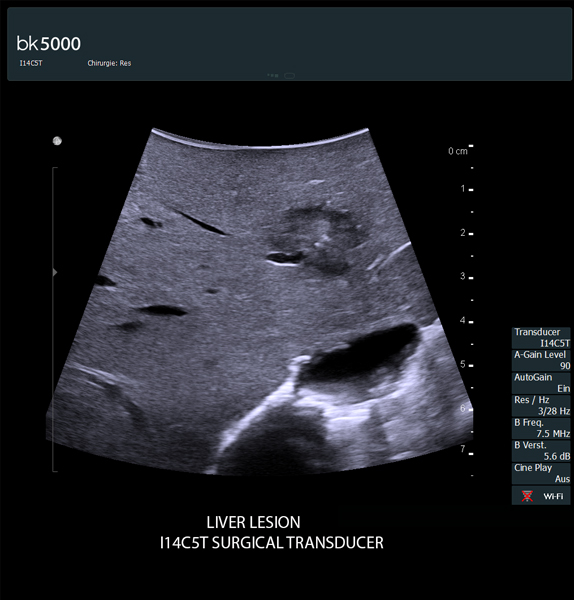

- Ngoài ứng dụng hình ảnh siêu âm chẩn đoán thông thường thì Đặc biệt được sử dụng trong phẫu thuật:

+ Điều trị Hủy u gan dưới hướng dẫn của siêu âm: Bằng sóng cao tần (RFA), Microwave ablation, sinh thiết gan, chọc hút dẫn lưu gan...